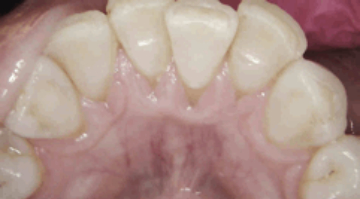

On July 7, 2016, when the patient returned, bleeding was reduced from 101 sites to seven sites, and deep pockets decreased from 37% to just 2%. The patient was then asked to incorporate the trays into her regular home care, using them once a day for 15 minutes.

Periodontal charting on July 7, 2016.